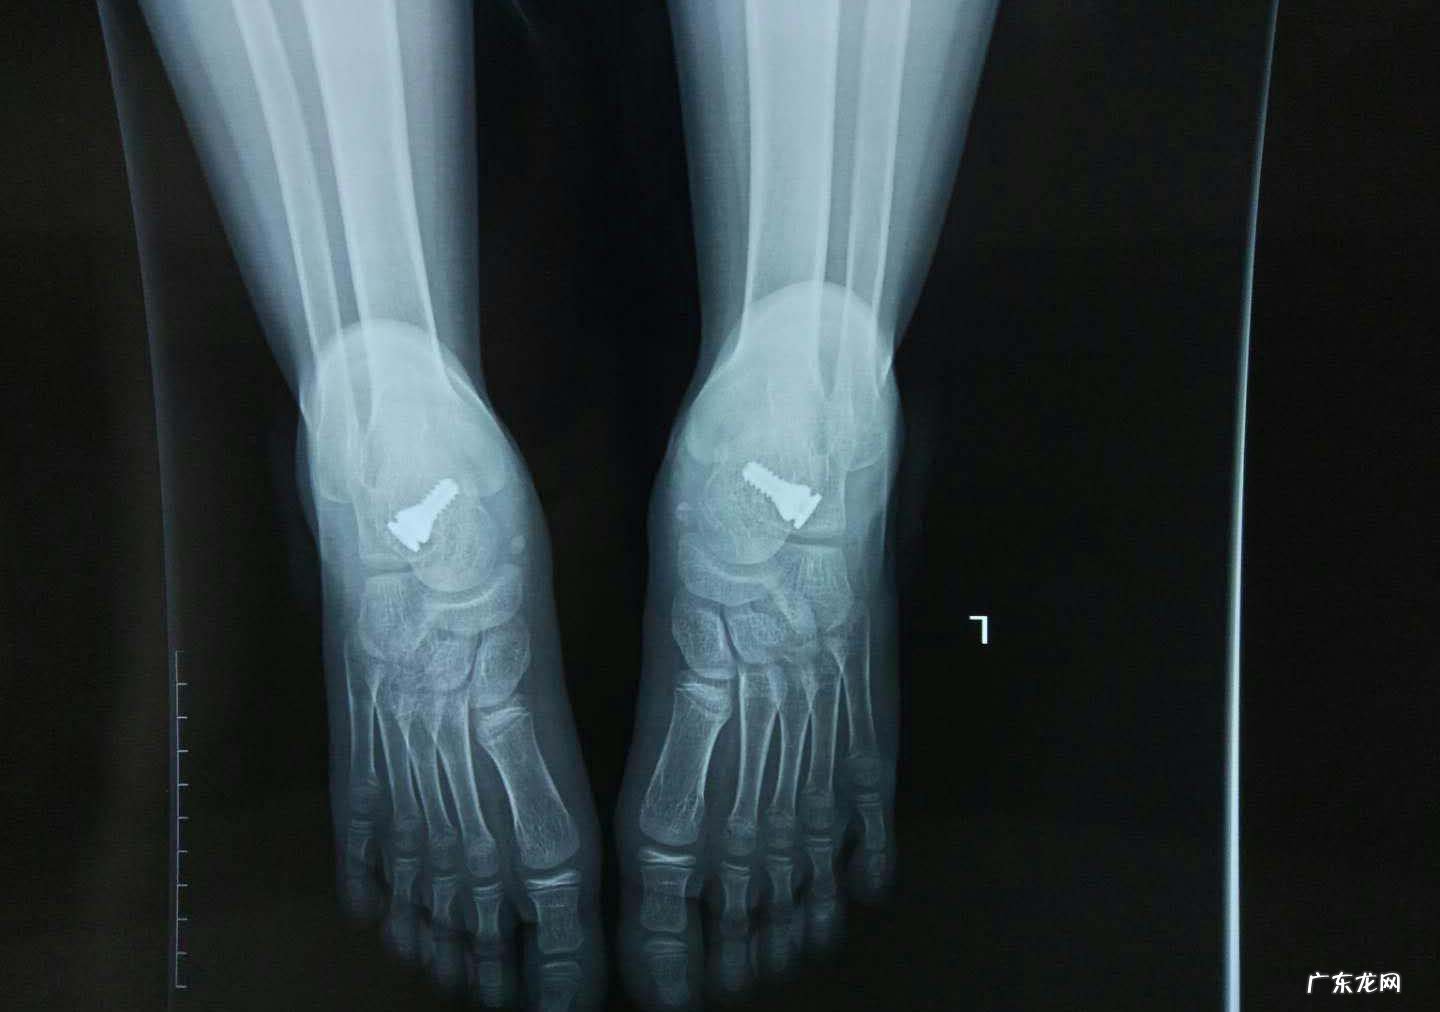

辅助检查方法主要是X线检查!

①有先天性足骨排列异常或足部创伤症、超限负荷、足部肌肉韧带软弱等病史 。②足部纵弓塌陷,足底扁平 。足跟外翻,行或久站易感疲乏、疼痛和压痛 。③足印检查无弓状缺损区,并确定平足型及程度 。④X线片显示足纵弓塌陷,跗跖骨轴线关系改变 。